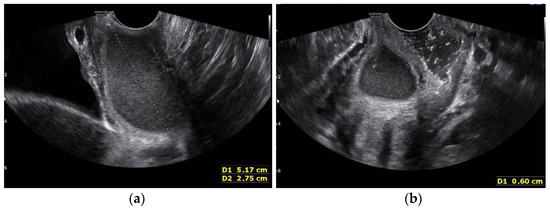

Figure 6. Transvaginal USG image one month after the initial visit. (a) More substantial fluid collection in the right side obstructed hemi-vagina; (b) Transvaginal ultrasonogram image showing the thickness of the vaginal septum to be approximately 6 mmn (measured with +calipers).

One month later, three days before the planned operation, the patient again visited ER due to severe lower pelvic pain. This time we were able to identify the bulging vaginal wall using a vaginal speculum exam and transvaginal USG (Figure 6a,b).